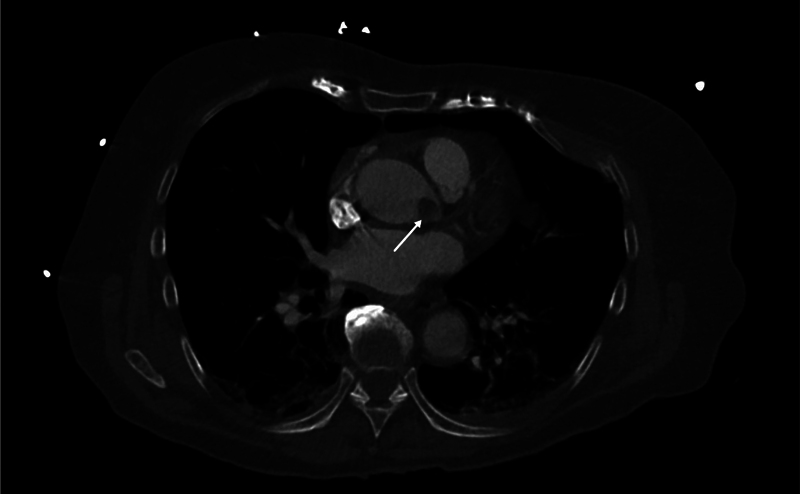

Symptoms of papillary fibroelastomas are often related to thromboembolic events but are rarely caused by a mechanical impairment of blood supply by the tumor itself. We describe a case of a papillary fibroelastoma in a 91-year-old female patient leading to a cardiac arrest through intermittent occlusion of the left coronary artery.

Abstract Image